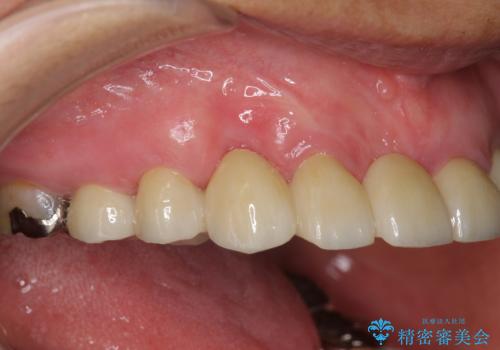

過度な咬合力は歯を失う元です。

ブリッジによる欠損補綴を行ったのち、ナイトガードを夜間装着していただき歯を守ります。